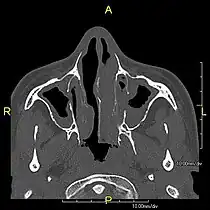

- Axial CT image showing chronic sinusitis in an individual with Kartagener syndrome